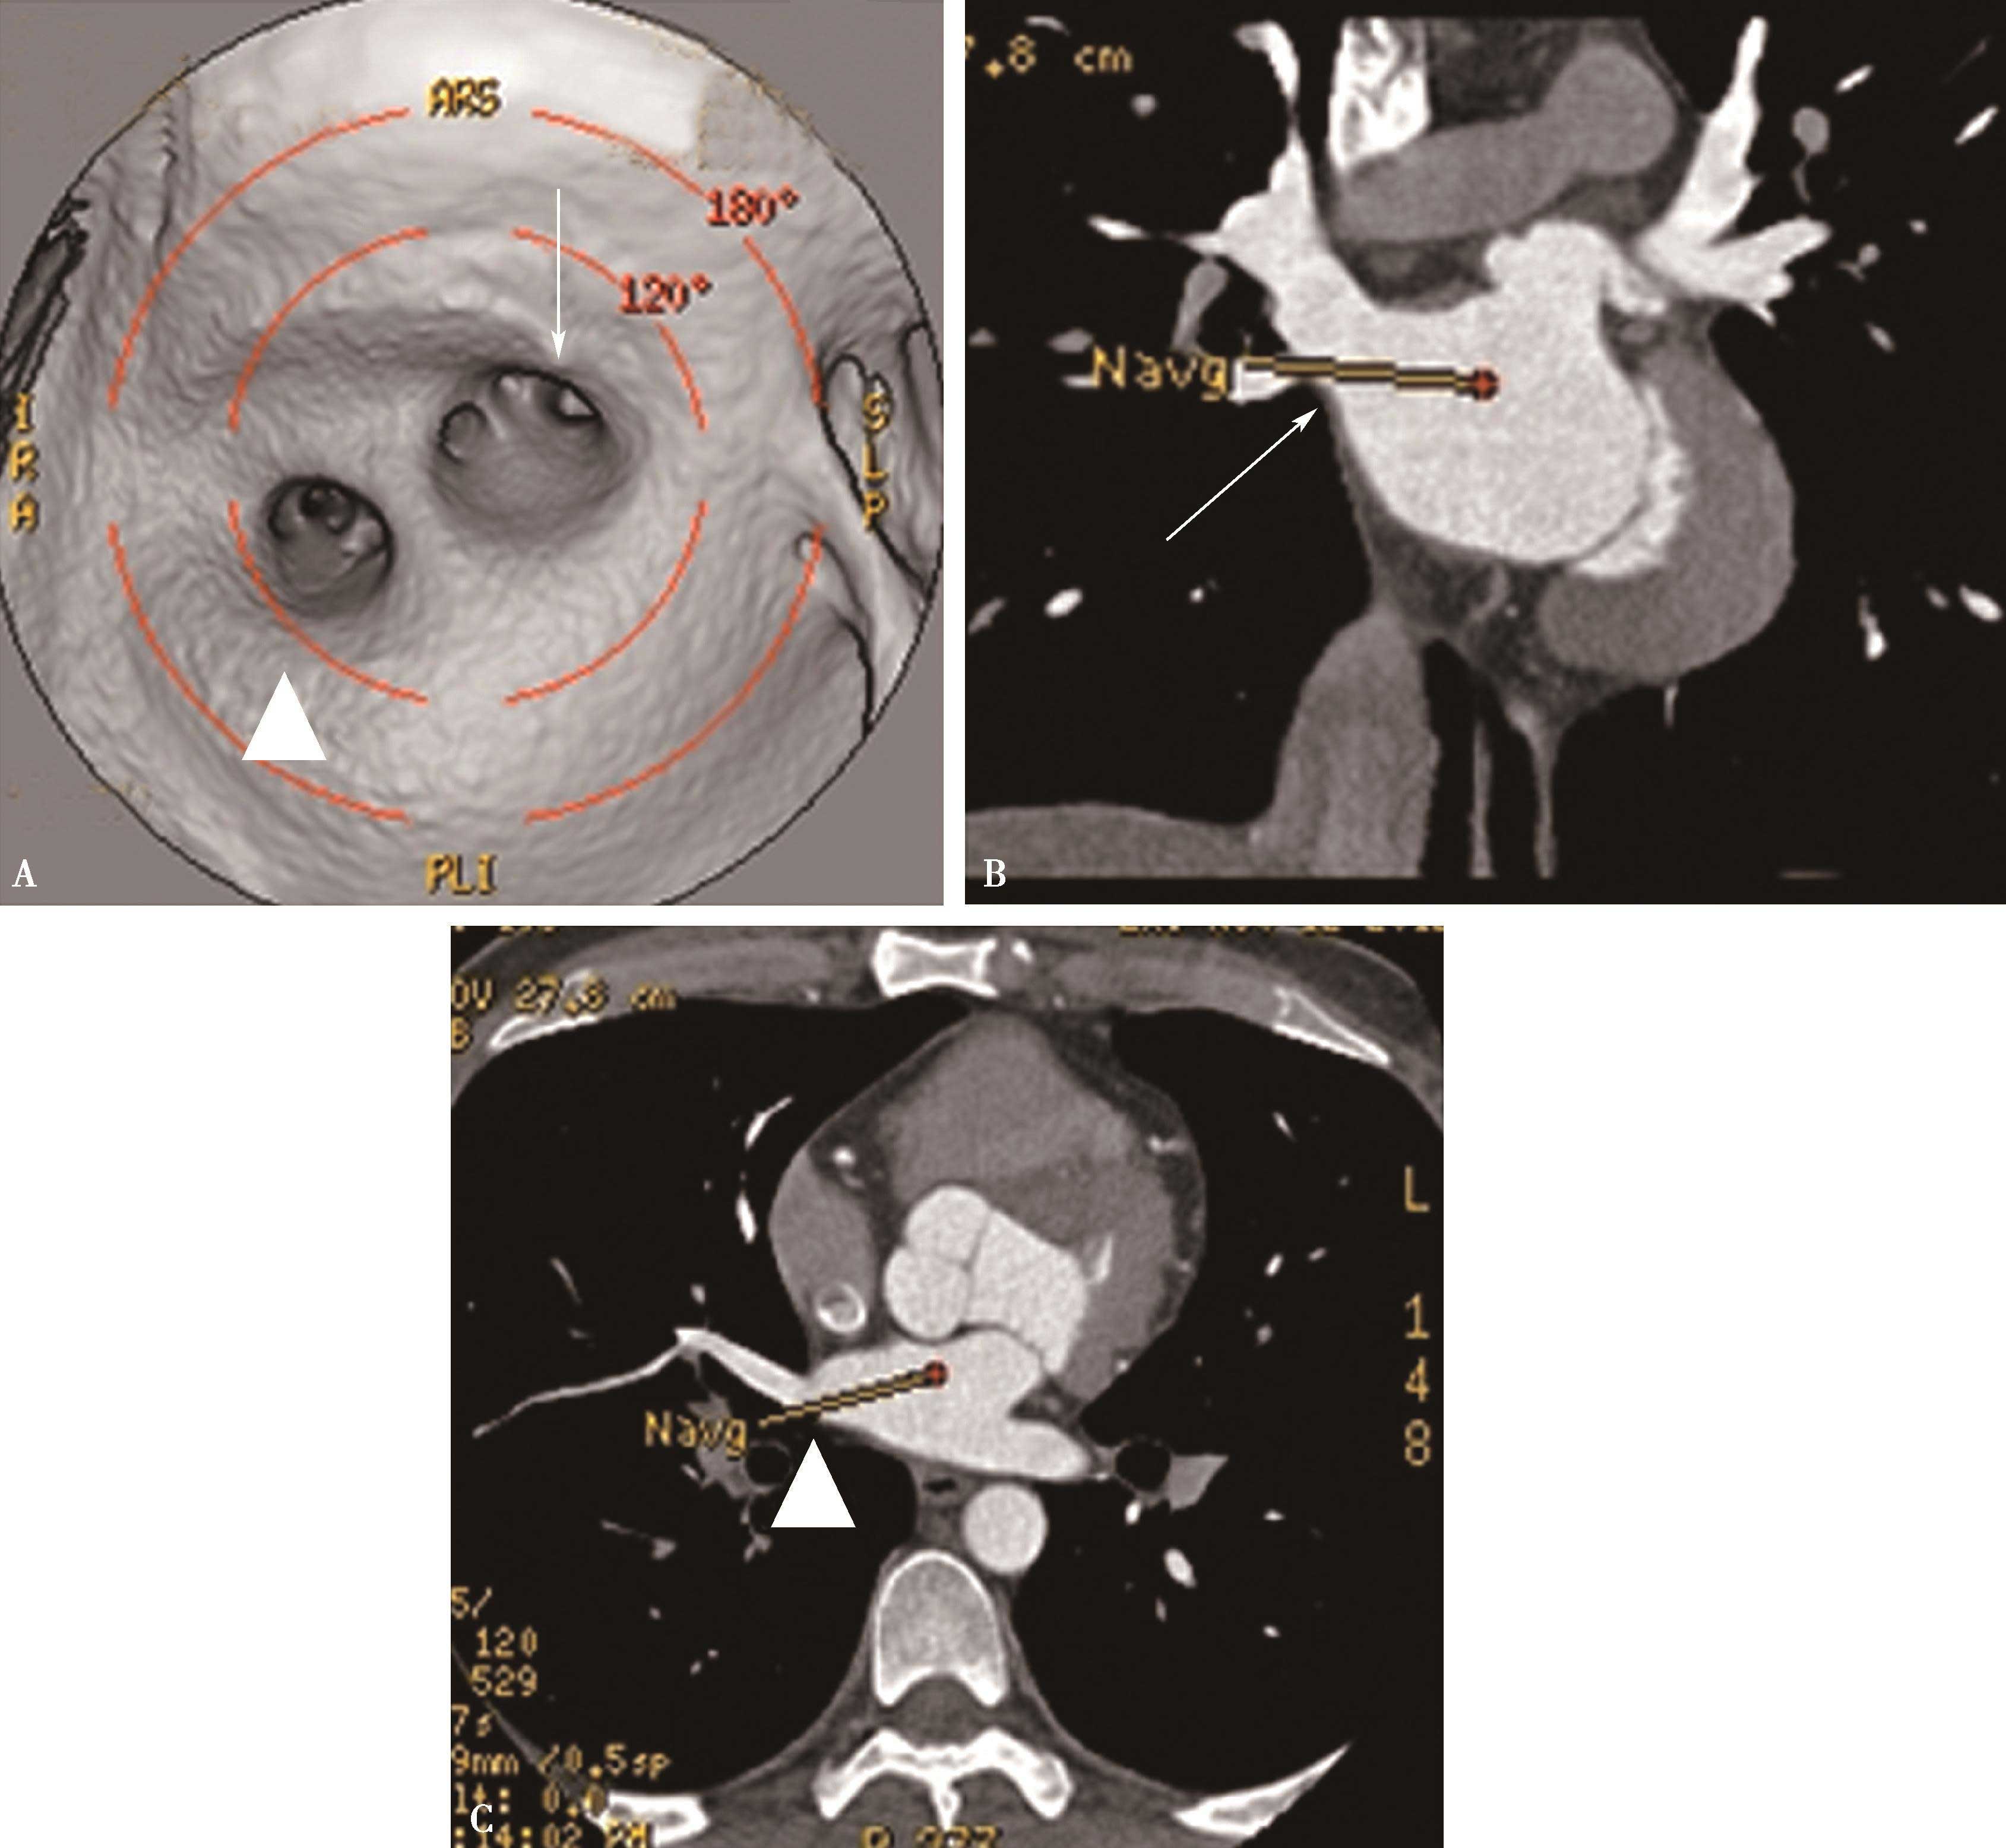

五、多排螺旋CT肺静脉造影方法

多排螺旋CT肺静脉造影检查多用于:①左心房-肺静脉检查,用以检查左心房,左心耳和肺静脉的解剖,评价肺静脉,评估左心房大小,检出左心房(耳部)血栓,指导临床诊断及射频消融治疗;②肺静脉疾患:肺静脉瘤,肺静脉狭窄,闭塞;回流异常等(包括先天性或获得性)。CT检查可以减少对有创检查的依赖、减少患者负担,有重大的优势。

(一)多排螺旋CT肺静脉造影检查方法

1.扫描的范围 从主动脉弓上水平到心脏膈面。

2.主要参数 以64排VCT为例,增强扫描参数设定为:电压120kV,电流400~600mA,机架转速0.35秒/圈,螺距为0.984∶1,准直器宽度为2.5mm,重建层厚0.625mm,视野(FOV)为25cm,矩阵512×512。由于采用的是智能监测跟踪技术。

3.扫描采用智能对比剂跟踪技术,监测层面设定在左心房的层面,ROI定为左心房,触发阈值定义为100~120HU。

4.对比剂 对比剂浓度320~370mgI/ml,采用单筒高压注射器团注,流率为4.0~5.0ml/s,对比剂总量为70~90ml。

5.一期扫描 当ROI的CT值达到阈值时启动增强扫描程序。第一期扫描得到完整的肺静脉-左心房图像。如果达到诊断目的,可结束扫描(图8-1-11)。

图8-1-11 肺静脉CTA检查

A.上肺静脉(↑);B.下肺静脉(↑);C.肺静脉最大密度投影。LSPV:左上肺静脉;LIPV:左下肺静脉;RSPV:右上肺静脉;RIPV:右下肺静脉